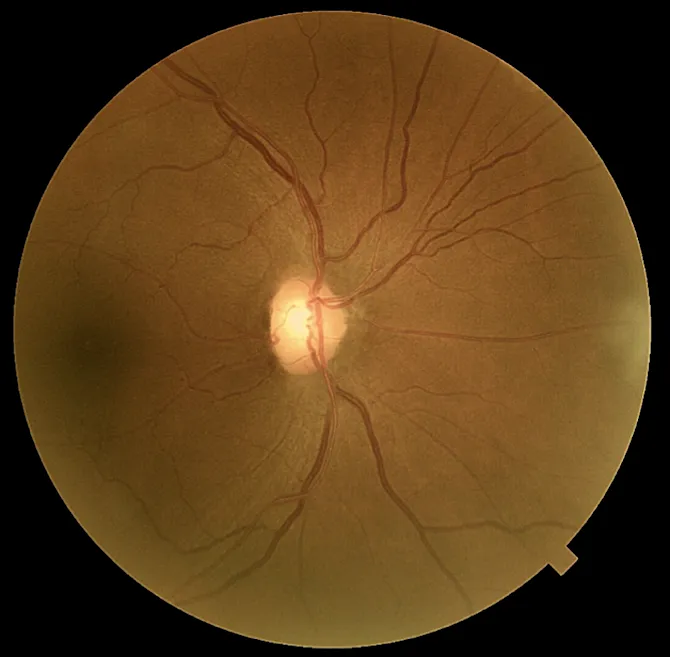

Les mesures de pression intraoculaire du patient, prises avec l'OCT Solix ont varié de 22 mmHg à 29 mmHg au cours des trois dernières années avec une PIO maximale de 25 mmHg OD et 29 mmHg OS. La pachymétrie est mesuré à 513 µm OD et 514 µm OS. Ses têtes de nerf optique étaient roses et distinctes avec des rapports C/D mesurant .55V/.50H OD et .65V/.55H OS. Un examen OCT-A a été réalisée sur le Solix pour évaluer davantage la présence de glaucome par rapport à l'hypertension oculaire.